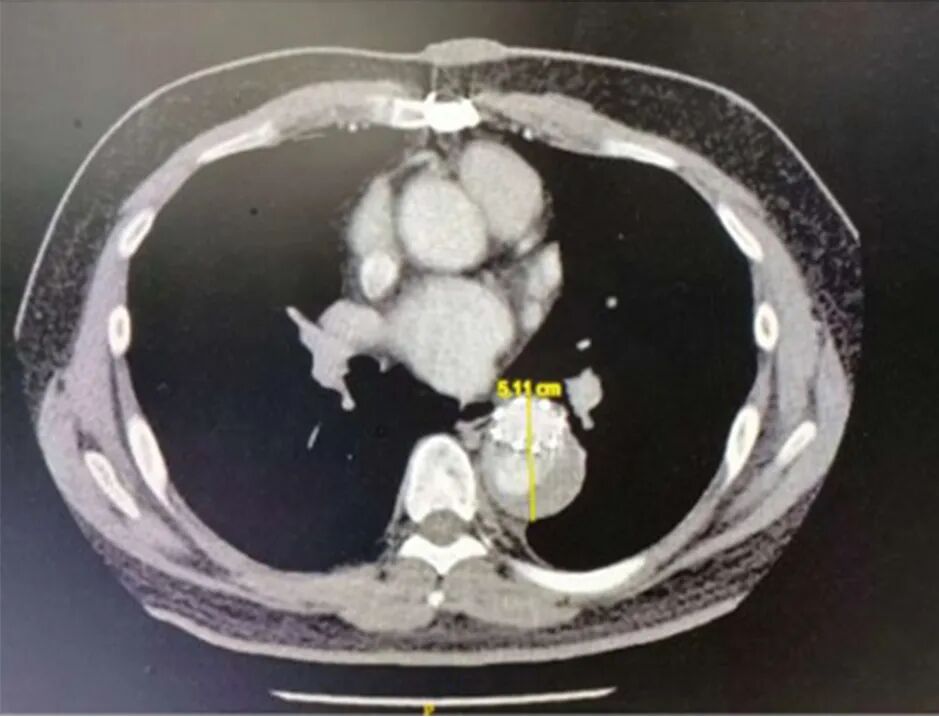

上午直播的最后一台手术广东省人民医院郭惠明教授。患者为66岁男性,活动后气促1年,药物治疗未见缓解,既往有房颤、高血压病史。心超示:1.肥厚型心肌病,室间隔19 mm;2.二尖瓣重度返流,后叶拴拽;3.三尖瓣中度返流;4.轻度肺动脉高压,PASP 40mmHg;5.左房内径61 mm。心脏CTA提示室间隔非对称性肥厚,心脏MR显示增强延迟,心电图见心房颤动,肺为中重度混合性通气功能障碍。为避免术后SAM现象及左室流出道梗阻,同时尽可能保留患者胸廓完整性、减少出血及肺功能损伤,郭惠明教授决定行全腔镜扩大室间隔心肌切除+二尖瓣置换+三尖瓣成形+左心耳缝闭术。

术中经股动静脉插管建立体外循环,经右胸第四肋间进入胸腔,切口长约4cm。由于患者术前心超提示室间隔基底段明显增厚,仅行二尖瓣手术或致左室流出道梗阻。在充分评估多模态影像学资料并参考基于心脏CTA的三维重建模型,郭惠明教授在经二尖瓣切除肥厚左室心肌后在,以29 #生物瓣置换二尖瓣、29 #成形环环加固三尖瓣环。主动脉开放后各吻合口止血顺利,经食管心脏彩超见左室流出道疏通效果满意、二尖瓣及三尖瓣未见返流,术后心电图未见完全性房室传导阻滞。

在本次直播中,郭惠明教授再次演示了高难度的全腔镜复杂手术。该团队采用基于心脏CTA重建的心肌模型可精确评估肥厚心肌位置、厚度、深度及宽度,从而为全腔镜下操作带来实质性帮助,增强了效果与安全性。郭惠明教授也借这一新技术鼓励年轻心外科医生拥抱新进展,使更多患者受益。